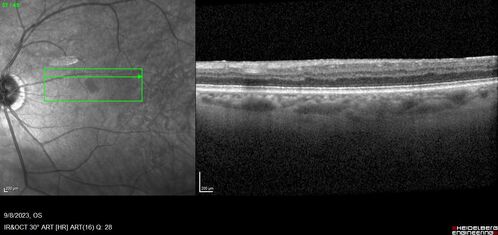

Paracentral acute middle maculopathy - isolated

83 year old man New spot in the vision yesterday left eye.

Medical Hx: Pure Hypercholesterolemia

Systemic Meds: Crestor.

VA OD: Dcc20/20

VA OS: Dcc20/20

IOP: TP: OD:19 OS:10

Isolated PAMM lesion